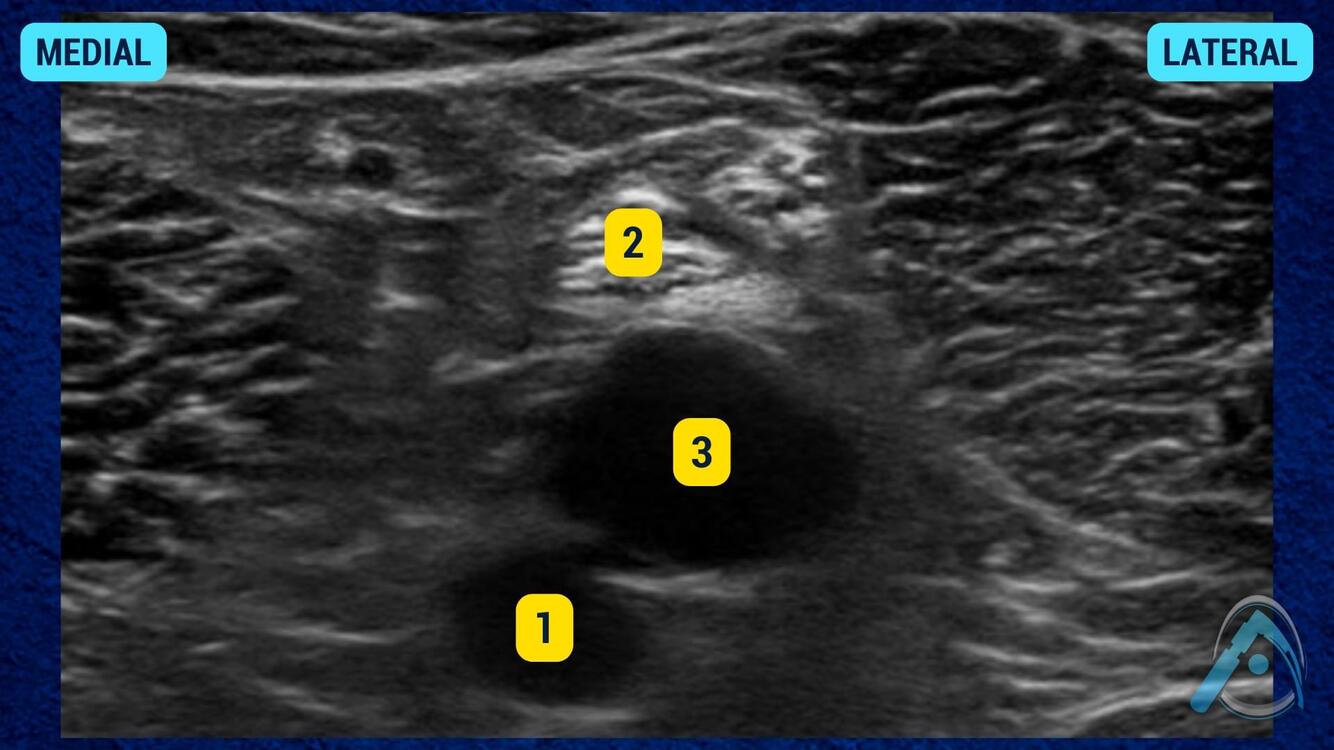

Num bloqueio de membro inferior com auxílio de ultrassonografia, o que são as estruturas em destaque?

1 - nervo femoral; 2 - atéria femoral; 3 - fáscia ilíaca